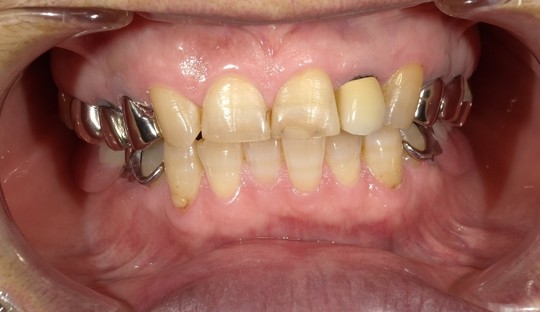

年齢:70代女性

治療内容:奥歯の銀歯が気になるという主訴で、右上中央から3,4,5番目をe.maxにより修復

治療期間/通院回数:3回

費用: e.max クラウン 110,000円x3本 ※2025年7月現在の価格